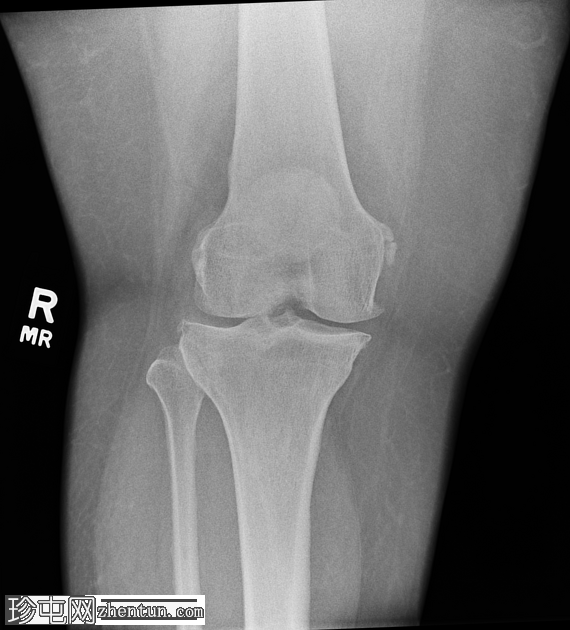

正位片

右膝中度骨关节炎(3级),表现为内侧胫股关节和髌股关节间隙狭窄,边缘可见骨赘、髌骨骨刺和胫骨棘突。

内侧副韧带近端附着处股骨内侧髁附近可见长圆形软组织骨化,提示为佩莱格里尼-斯蒂达(Pellegrini-Stieda)损伤。